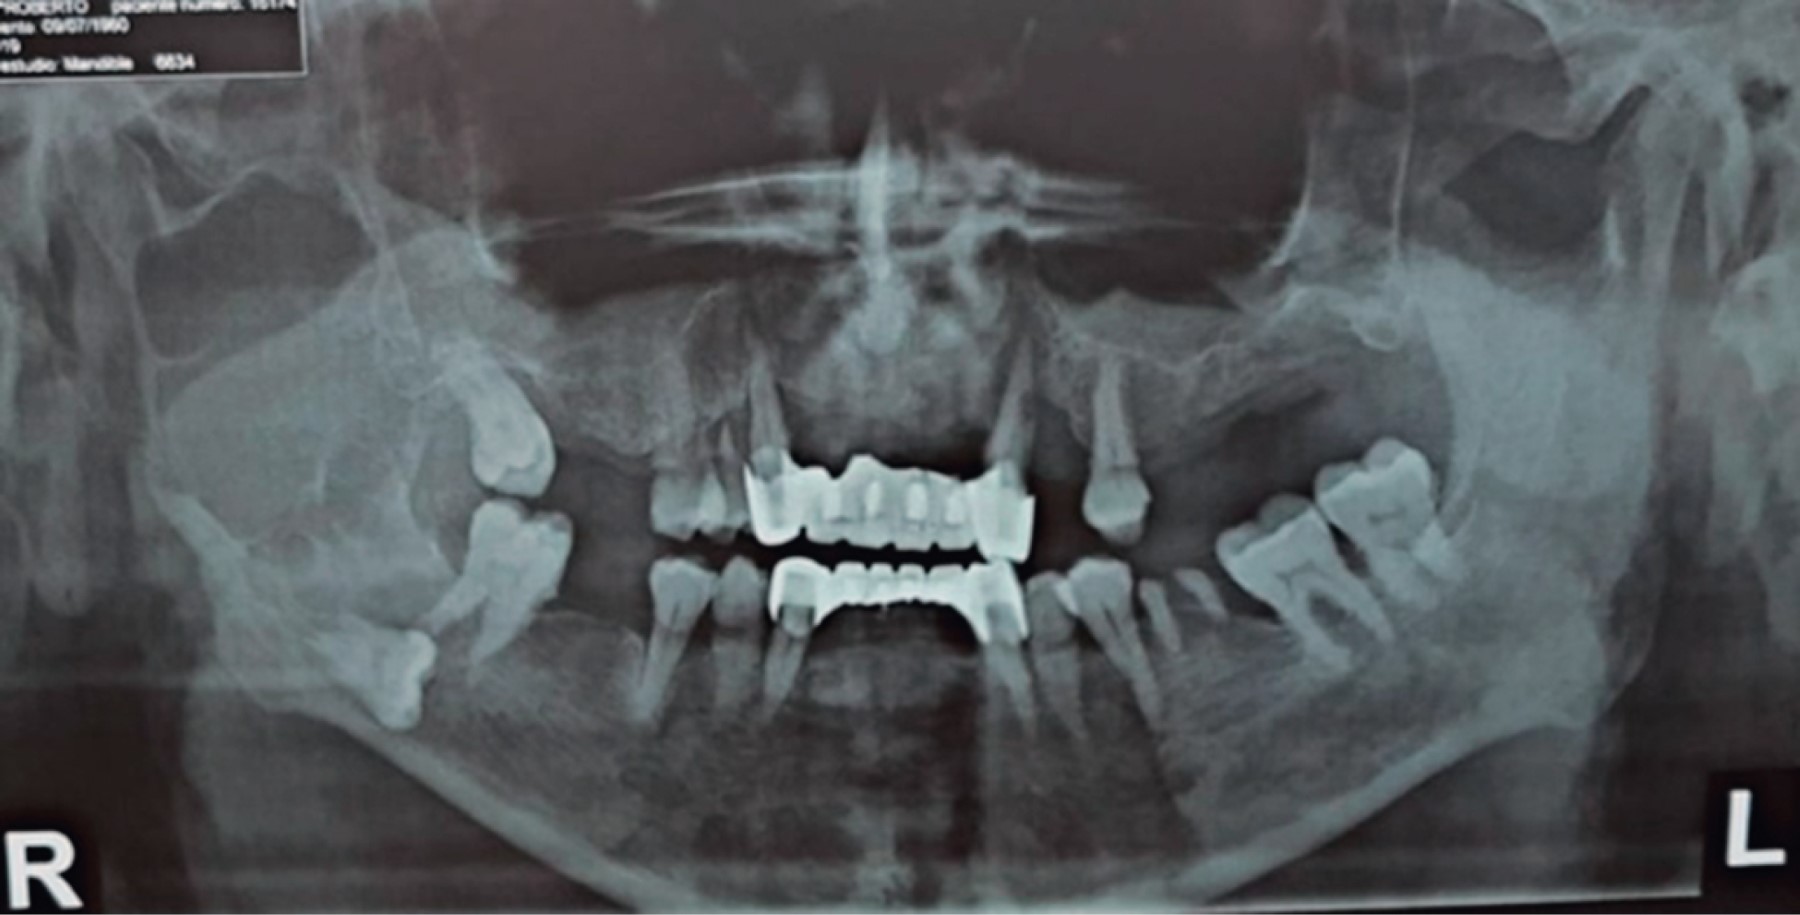

Inició padecimiento 19 meses previo a su primera valoración refiriendo chasquido súbito tras apertura máxima de la cavidad bucal, presentando dolor y aumento de volumen en la región posterior de la mandíbula derecha. En ortopantomografía se observa una zona radiolúcida, multilocular que abarca la rama ascendente derecha de la mandíbula y porción posterior del cuerpo mandibular con desplazamiento de tercer molar hacia borde cervical mandibular (Figura 1). En tomografía computarizada se observa lesión patológica multilocular que abarca la rama ascendente de la mandíbula, apófisis coronoides y hasta el cuello del cóndilo, la de mayor diámetro es de 35 × 32 mm con perforación de corticales casi en su totalidad y expansión de las corticales residuales (Figura 2). Se procede a realizar toma de biopsia incisional con un resultado de ameloblastoma folicular con datos de atipia celular (Figura 3), por lo que se decide solicitar gammagrama óseo que muestra una captación anormal en la rama mandibular derecha desde el cóndilo que correlacionan con la tumoración presente, así como un resultado negativo a la extensión metastásica ósea (Figura 4). Se decide realizar hemimandibulectomía y colocación de placa de reconstrucción con componente condilar. Se solicita estereolitografía para la preconformación de la placa de titanio y así disminuir el tiempo transoperatorio y márgenes de error en su colocación (Figura 5). Bajo anestesia general balanceada (AGB) se realizó fijación intermaxilar con ayuda de tornillos y cadena elástica. Se hizo incisión submandibular, se diseco el tejido por planos hasta llegar al hueso mandibular, se procedió a realizar hemimandibulectomía derecha, posteriormente se colocó placa de reconstrucción (Medartis MODUS®) con bloqueo y dispositivo condilar para reconstruir el cuerpo y rama mandibular (Figura 6), se verificó la oclusión, y el ajuste de la placa mediante toma de radiografía de control transoperatoria (Figura 7), se suturó por planos con sutura Vycril 3.0 y Polipropileno 5-0 para confrontar tejidos. El postoperatorio cursa sin complicaciones, por lo que se decide su egreso hospitalario para continuar su tratamiento por consulta externa en servicio de cirugía maxilofacial (Figura 8). El resultado histopatológico de la muestra completa reporta un espécimen formado por islas y cordones de epitelio ameloblástico de aspecto folicular y acantomatoso y displasia leve en un tejido conectivo fibroso denso bien vascularizado. Dos años después del procedimiento quirúrgico el paciente se encuentra asintomático y sin datos clínicos o radiográficos de recidiva.

Figura 1